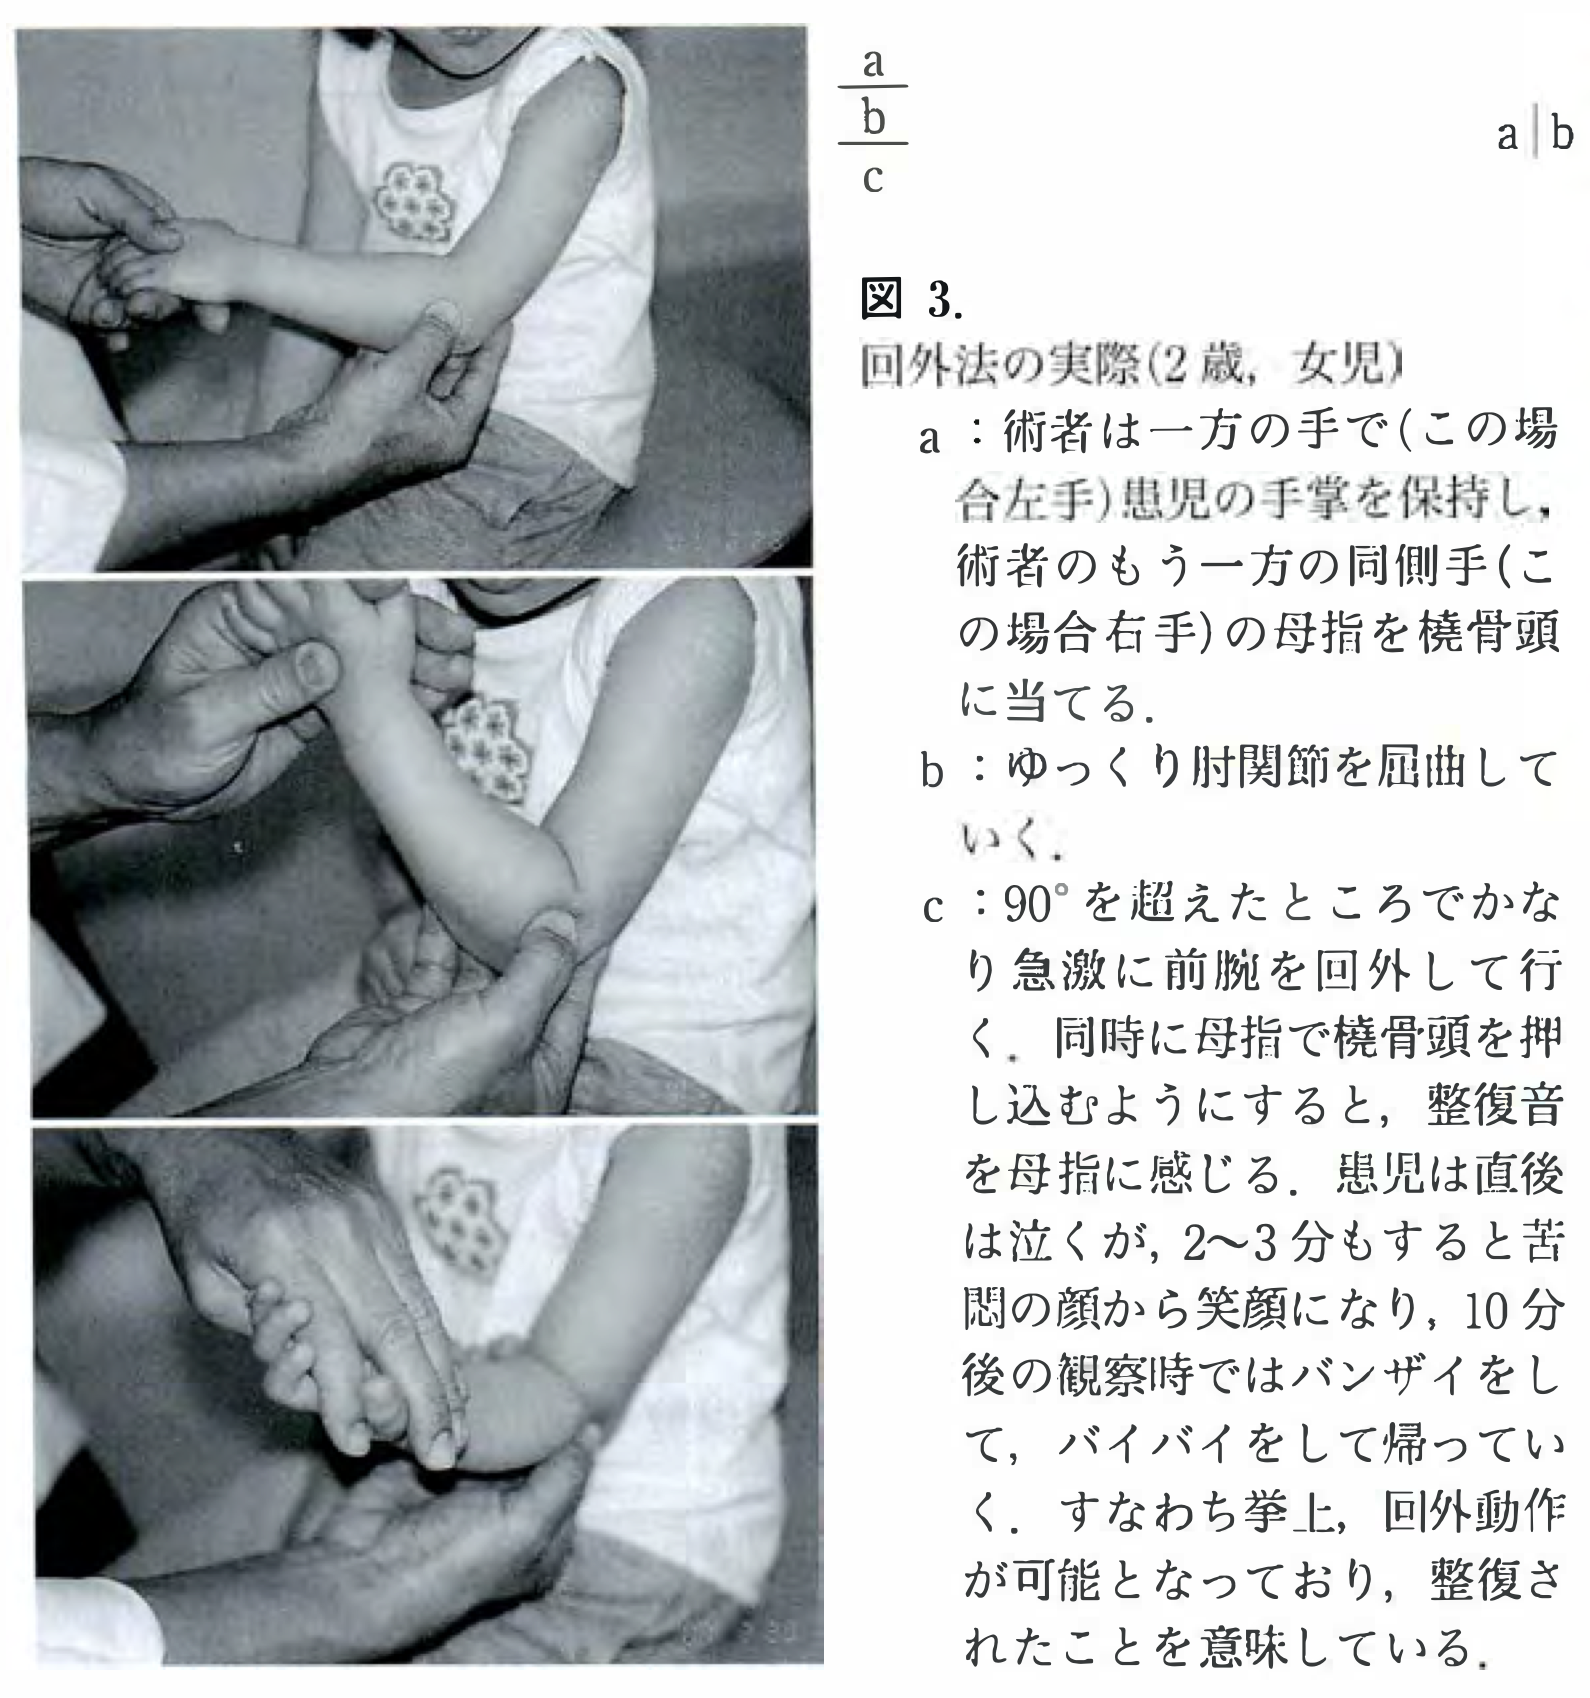

8時から後輩医師と一緒に朝の病棟回診を行いました. 元々は, 腰椎の圧迫骨折で入院中の超高齢の患者さんが, 意識低下と腕の麻痺があるのが判り, 脳梗塞を疑って, 頭部のMRIを撮像するようにオーダーしました.